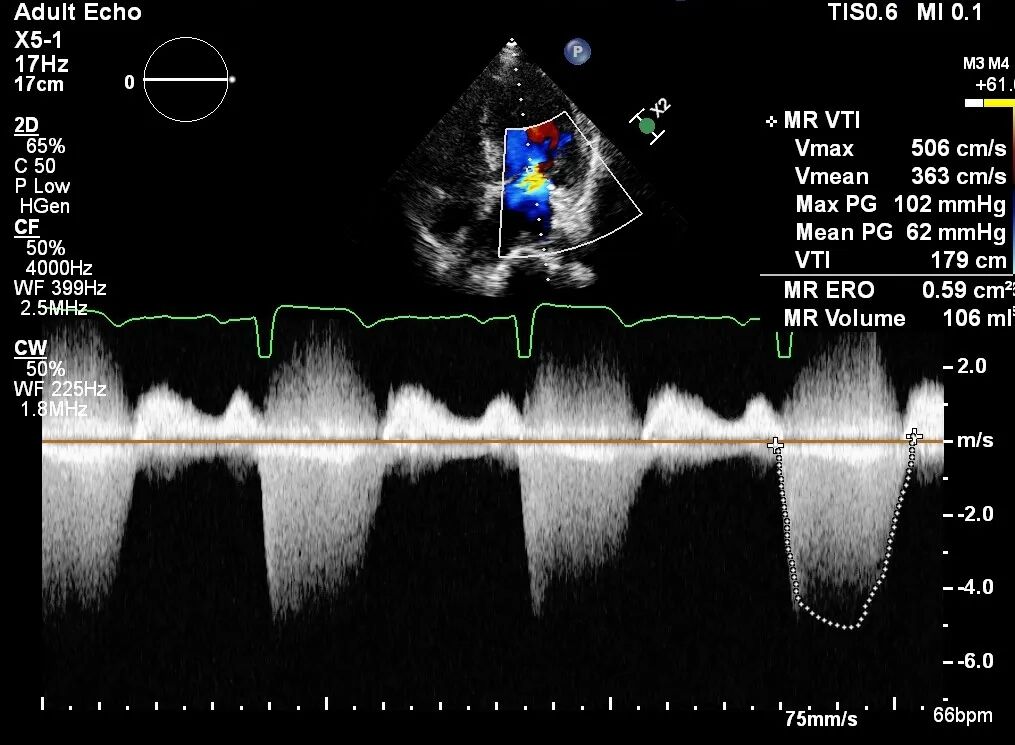

术前TTE提示

二尖瓣重度反流,EROA=0.59 cm²;RV=106ml;三尖瓣少-中等量反流,PASP: 42 mmHg;左心增大,左室收缩功能减弱。